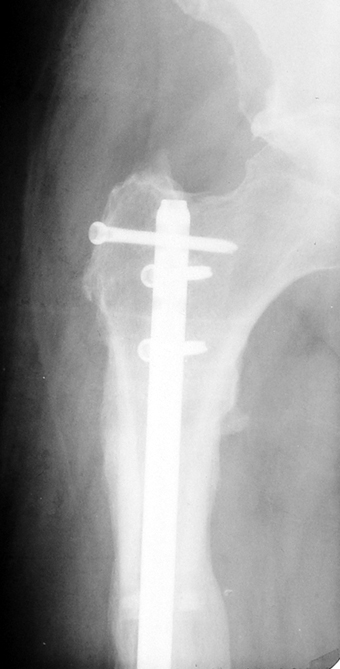

Eksternal fiksatör ile geçen süre (eksternal fiksasyon indeksi), gereken distraksiyon miktarına bağlıdır ve bu süre boyunca bazı komplikasyonlarla karşılaşılabilir. Distraksiyon dönemi sona erdikten sonra, distraksiyon süresinin iki katını aşan konsolidasyon döneminde hastalar eksternal fiksatörü zorlukla tolere edebilirler. Yeterli konsolidasyon sağlanmadan eksternal fiksatör çıkartılırsa ise kırıklar, deformite ve kısalık oluşabilir. Hastanın fiksatör ile birlikte geçirdiği sürenin azaltılması ve böylece hasta konforunun ve aktivite düzeyinin arttırılması için intramedüller çivi üzerinden uzatma yöntemi uygulanmaktadır. Bu yöntemde distraksiyon dönemi sona erdiğinde kemiğin içindeki çivi statik olarak kilitlenmekte ve eksternal fiksatör çıkartılmaktadır. Stabilizasyon intramedüller çivi tarafından sağlandıktan sonra konsolidasyon dönemi gerçekleşmektedir. Bu şekilde hem eksternal fiksatörün uzun süre kalmasından hem de erken çıkartılmasından kaynaklanan komplikasyonların önüne geçilmektedir.

Vaka 2